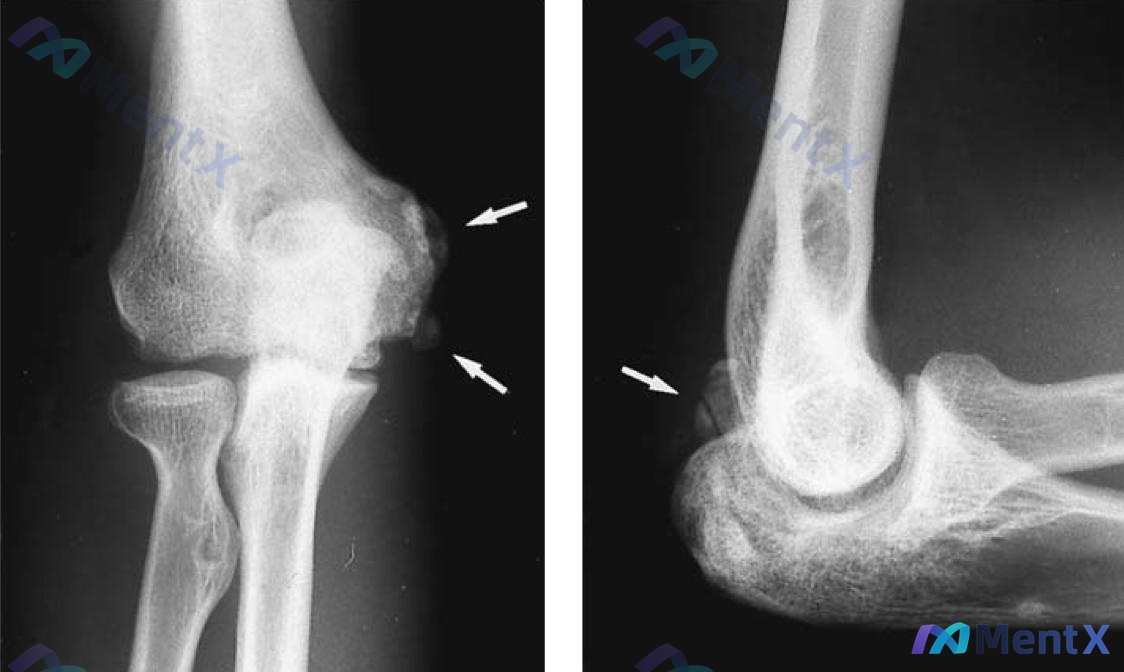

整理到一个创伤后肘关节的病例,影像和病史都比较典型,拿出来和大家讨论一下。 基本情况 - 27岁男性,摩托车手 - 10个月前车祸致右臂骨末端损伤(具体原文为“住院性监禁”,结合上下文应为肱骨远端/肘部损伤),接受了非手术治疗 本次就诊情况 - 主诉:活动范围有限 + 持续性疼痛 - 查体:右侧肘关...